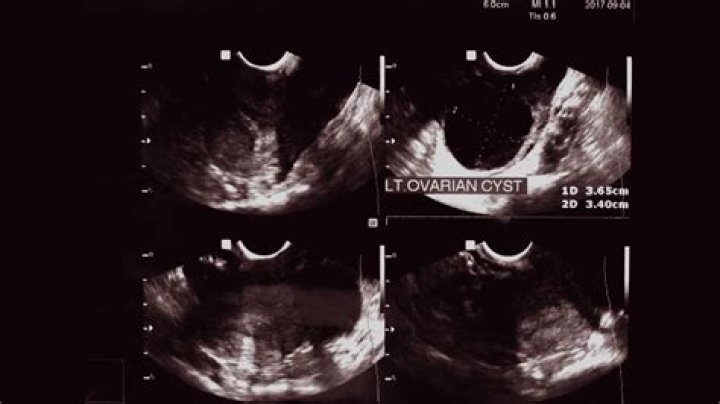

Ovarian cysts can sometimes be detected during a pelvic examination, although an imaging test, usually a pelvic ultrasound, is necessary to confirm the diagnosis. Computed tomography (CT) scan or magnetic resonance imaging (MRI) are also sometimes used, but less commonly.

How do gynecologists check for ovarian cysts?

If your gynecologist suspects that your symptoms could be due to ovarian cysts the best way to diagnose these cysts is through a pelvic exam or by performing an ultrasound. The ultrasound will allow your doctor to examine the abdomen in detail to see if cysts are present.

2. Ultrasound. An ultrasound can pinpoint the location, size, and makeup of ovarian cysts. ...